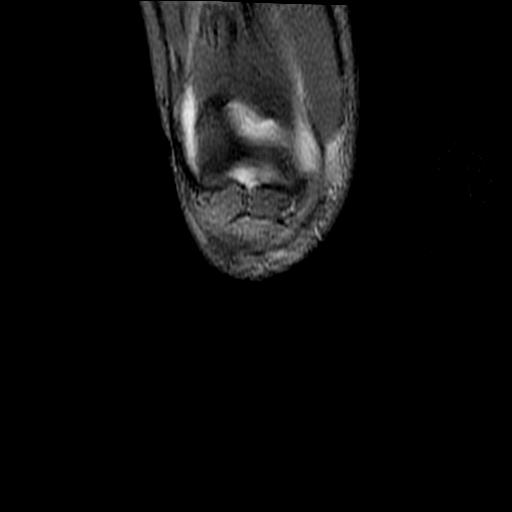

40岁男性,右膝关节外伤,x光平片示,髁间隆突撕脱骨折。

1、前交叉韧带撕裂;

2、外侧半月板后角撕裂;

3、关节腔积液。

髁间隆突撕脱骨折;内侧副韧带损伤。

1、内侧副韧带撕裂;

2、前交叉韧带撕裂;

3、滑膜炎伴关节腔积液。

1、前交叉韧、内侧副韧带撕裂;

3、关节腔积液。4、髁间脊撕脱骨折。